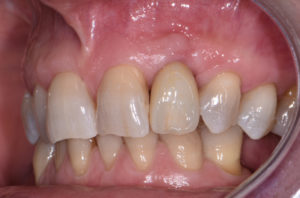

Durante il periodo di maturazione dei tessuti molli vengono apportate opportune modifiche ai profili del provvisorio, al fine di dare maggior spazio al tessuto gengivale (Figg. 44-47).

- Fig. 44

- Fig. 45

- Fig. 46

- Fig. 47